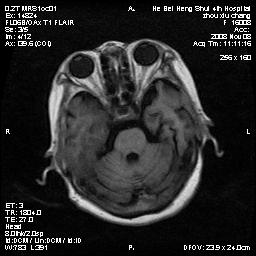

标题: MRI1883:女67岁,半年前曾患脑梗塞,治疗后好转,近3各月精

女67岁,半年前曾患脑梗塞,治疗后好转,近3各月精神恍惚。

两种可能:1,转移瘤,2,脑炎,建议增强扫描

形态及整体病灶看起来首先考虑转移瘤或淋巴瘤,但奇怪的是多个病灶周围均未见显著的水肿区,这不符合这两个肿瘤的特点,结合ct表现及患者病史有个人考虑是否有皮层下动脉硬化性脑病伴多发胶质增生可能.

不像占位性病变,考虑脱髓鞘改变

皮层下动脉硬化性脑病伴脱髓鞘改变!